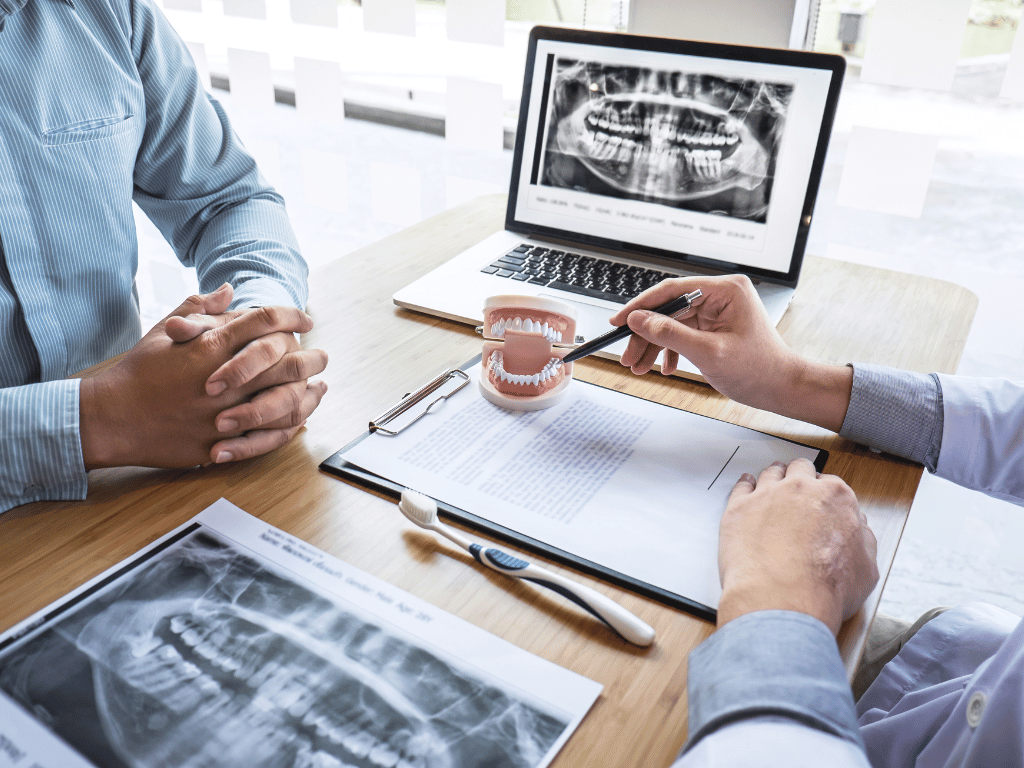

Patient Centred Dentistry.

Everything you need for a smooth visit , from what to expect at your first appointment to insurance, forms, and flexible payment options. At Mississauga Hanin Dental, we make your experience simple, clear, and stress-free.

General Dentistry

Healthy smiles start with strong foundations. At Mississauga Hanin Dental, we offer routine cleanings, exams, fillings, and gum care to keep your teeth in top shape. We focus on prevention, early treatment, and personalized care for lasting oral health.